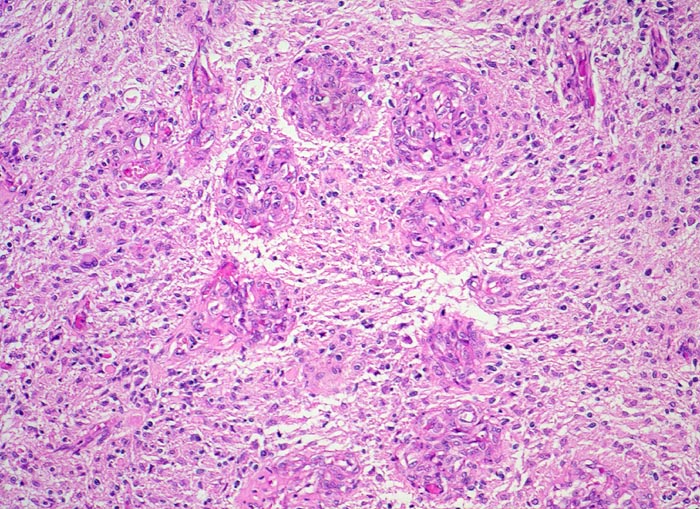

PathoPic ID 5202 - Glioblastoma multiforme (WHO IV)

Glioblastoma multiforme (WHO IV)

Für das Glioblastom typische zu einer Kette angeordnete glomerulumartige

Gefässknäuel.

Seit zwei Monaten zunehmende Persönlichkeitsveränderungen, Kopfschmerzen und progrediente fokal neurologische Zeichen.

Histologie

100